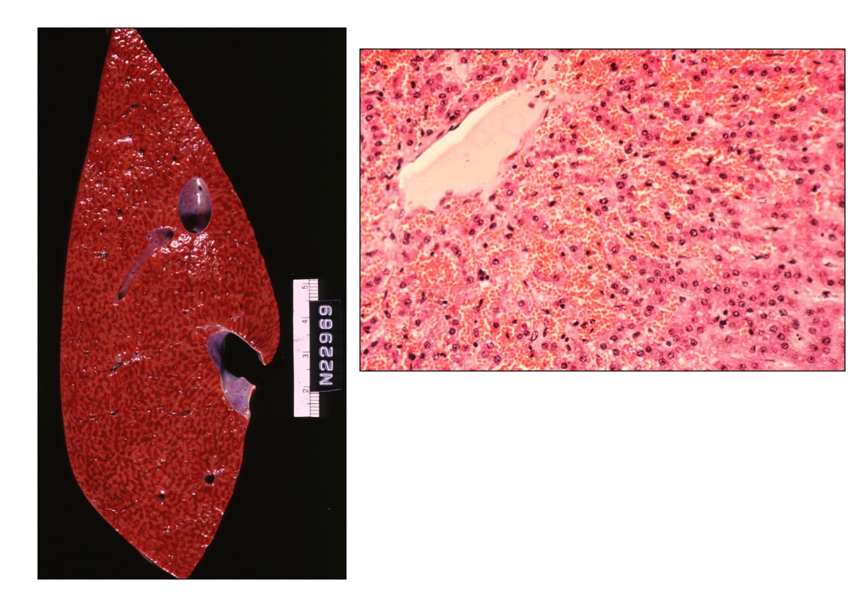

What is happening here? What side of the heart is involved? Provide a morphological diagnosis.

Passive congestion of the liver

Liver: congestion, diffuse, acute, severe

Right sided heart failure